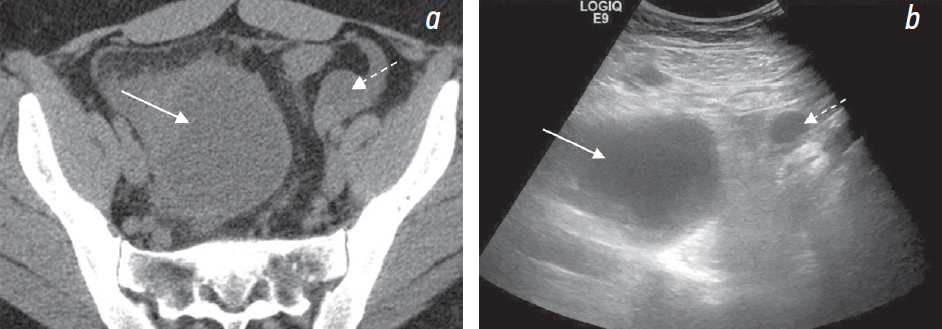

При УЗИ: свободная жидкость в брюшной полости (преимущественно около печени, в гепаторенальном кармане, в правом боковом канале толщиной слоя до 10 мм) и малом тазу (рис. 1, b, e). В области правых придатков определяется образование (размерами около 65 × 70 × 90 мм) с содержимым в виде мелкодисперсной эховзвеси («матовое стекло»), стенками неравномерной толщиной 7–10 мм с прилежащими по наружному контуру гипоэхогенными массами (сгустки?) (рис. 3, c). В околоматочном пространстве эховзвесь в жидкости идентична содержимому кисты в яичнике (рис. 4, а, b). Матка и левый яичник (рис. 2, b) без эхоструктурных особенностей. Паренхиматозные органы брюшной полости и забрюшинного пространства без УЗ-признаков структурной патологии. Заключение: УЗ-признаки могут соответствовать гемоперитонеуму вследствие разрыва кисты правого яичника (вероятно, эндометриоидной).

Рис. 4. На трансвагинальных сонограммах (а, b) показан идентичный сонографический паттерн жидкости в эндометриоидной кисте (стрелка) и свободной жидкости в маточно-пузырном пространстве (круг) и в маточно-прямокишечном пространстве (звездочка)

УЗИ позволяет с высокой степенью вероятности установить гемоперитонеум вследствие разрыва эндометриоидной кисты при наличии в жидкости околоматочного пространства эховзвеси, идентичной внутреннему содержимому кисты. Именно это и позволило в нашем случае на дооперационном этапе при УЗИ правильно предположить это патологическое состояние, которое было подтверждено интраоперационно, в то время как при КТ предположили новообразование яичника.